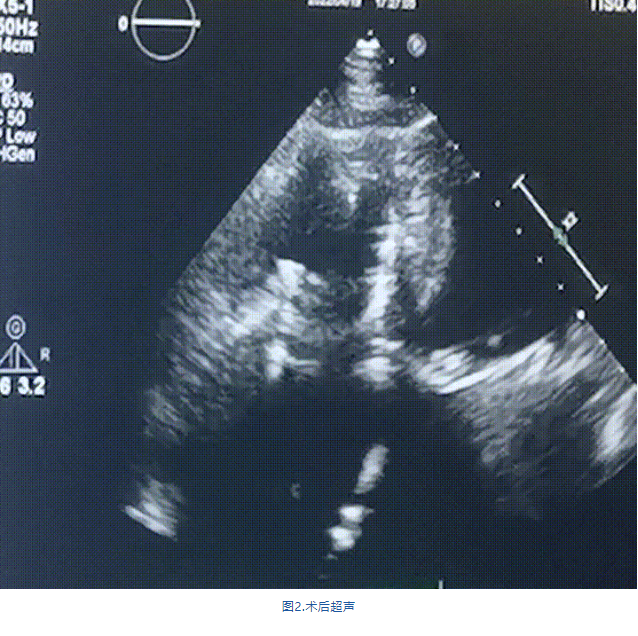

術(shù)前超聲提示:

1.右心、左房明顯增大;

2.二尖瓣人工機(jī)械瓣功能正常,無瓣周漏;

3.三尖瓣環(huán)巨大擴(kuò)張,收縮期瓣葉對合不攏,收縮期三尖瓣房側(cè)見大量反流信號,反流面積15-20cm²,TRVmax:240cm/s,跨瓣壓差:23 mmHg。